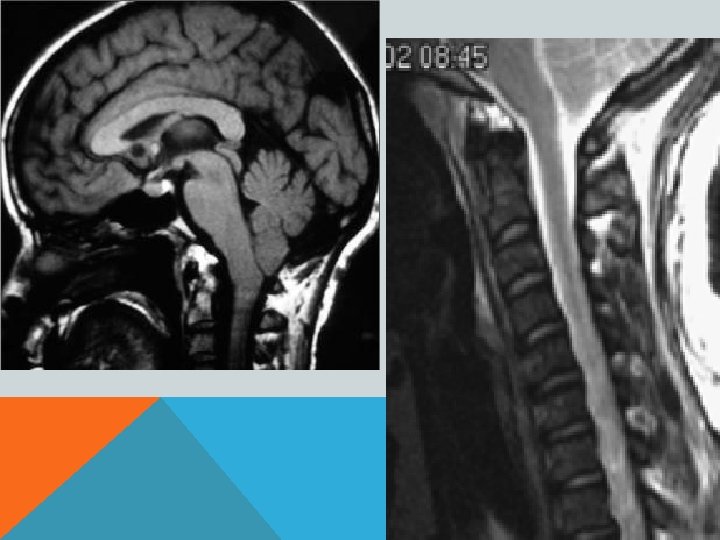

Диагноз подтверждает прежде всего МРТ. Дифференциальная диагностика • Опухоли спинного мозга обычно проявляются более локальной и быстро нарастающей симптоматикой • Травма спинного мозга • При боковом амиотрофическом склерозе двигательные расстройства никогда не сопровождаются выпадением чувствительности

ПОРОК АРНОЛЬДА-КИАРИ 1 Увеличение миндалин мозжечка, их опущение в большое затылочное отверстие и далее, в спинномозговой канал- «нижний» вариант. Характерно образование сирингомиелической полости в шейном отделе спинного мозга. Основные клинические проявления- сирингомиелия.

ПОРОК АРНОЛЬДА-КИАРИ 2 Увеличение миндалин мозжечка, их опущение в большое затылочное отверстие и далее, в спинномозговой канал. «Щелевидный» 4 -й желудочек. Гипоплазия подушки моста мозга. Гипо-/аплазия мозолистого тела. Сирингомиелическая полость в шейном отделе спинного мозга. Фенестрация фалькса (серпа мозга) и т. д. В 70% сочетается со спинномозговой грыжей.